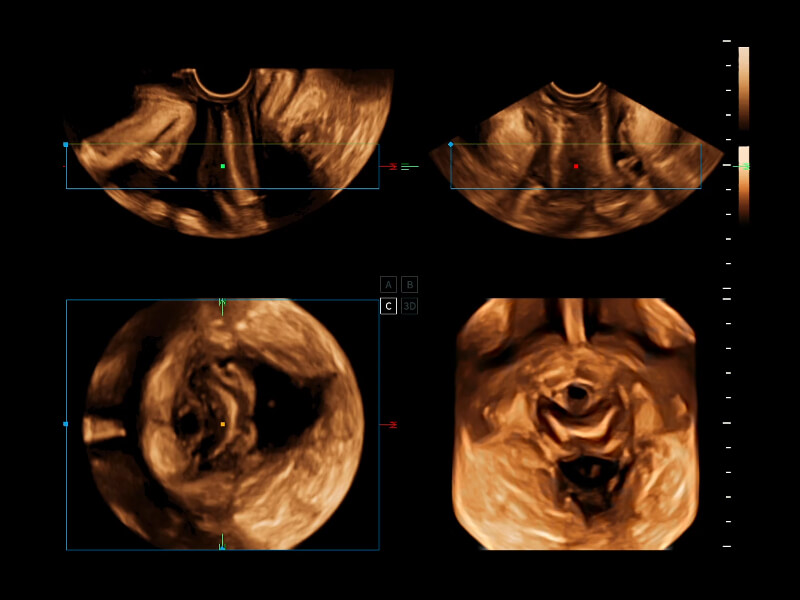

作为开立医疗全新打造的超高端旗舰超声产品,从探头抬起唤醒开启扫查到多维探头发射接收,通过先进的场成像发射、自适应聚合重建等技术,基于RF Data原始射频数据在图像生成、高端功能等方面实现突破,为妇产科、儿科提供全方位临床解决方案。

丰富的血流动力学检测技术,可在不同医疗场景中高效捕捉血流信号,助力临床诊疗。

在传统血流的基础上优化扫查和算法策略,能够更好的抑制组织信息,提炼红细胞运动信息,得到更高帧频,高灵敏度和分辨率的血流信号,还原更真实的血流动力学。

通过光照模型,使二维血流显示出立体的效果,增加血流的敏感性、成束性,减少外溢。可以和其他不同的血流技术联合使用,融合不同技术的优势。轻松应对微小血管,增强血流的立体效果,提升视觉敏感性。

通过创新的Matrix E自适应滤波算法,能有效滤除软组织和噪声信号,最大限度保留超低速微细血流的信号;结合超长时间域算法,极大提升细微血流的敏感性和空间分辨率,更真实的反应组织、包块的血流灌注情况。